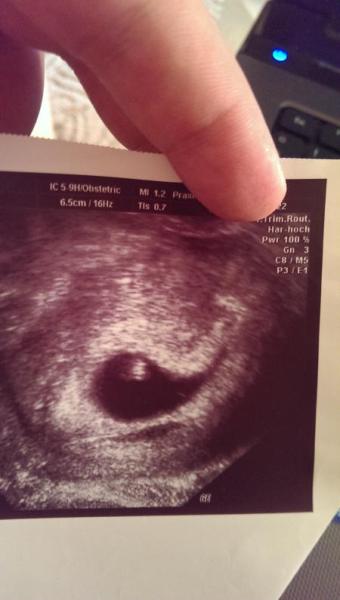

Bild zu

Sorry, aber 5+1 SSW passt nun gar nicht zum Ultraschallbild. Bei 4+5 konnte man bei meinen Schwangerschaften gerade eine Fruchthöhle sehen.... und schon gar nicht, ob gesund oder nicht...was für ein Quatsch.... Den Finger auch schön über das Datum....

Sorry, aber ich kaufe dir das auch nicht ab. Warum ist bei dem Bild denn das Datum verdeckt? Und wie Anfang der 6. Woche sieht das auch nicht aus. Vielleicht kannst du anderen was vormachen, mir nicht. Unglaublich, was Menschen sich einfallen lassen. Man man man... Tipp: lerne die deutsche Rechtschreibung incl. Punkt und Komma!